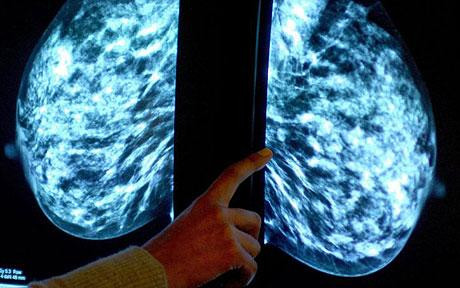

Nu numai credinta, ci si cel mai puternic antioxidant, astaxantinul, zis si "sangele lui Isus", ar putea fi leacul pentru combaterea cancerului. Studii recente au demonstrat ca este unul dintre cei mai buni regeneratori ai celulelor canceroase.

Potrivit numeroaselor carti de specialitate, astaxantinul si-a dovedit efectul prin optimizarea comunicarii intre celule, activarea enzimelor de faza I din ficat, plamani si rinichi care contribuie la combaterea nocivitatii substantelor carcinogene si modularea reactiei imunitare impotriva celulelor tumorale.

Studiile spun ca astaxantinul lupta impotriva radicalilor liberi de 550 de ori mai puternic decat vitamina E, de 60 de ori mai puternic decat vitamina C, de 53 de ori mai puternic decat beta-carotenul, de 18 ori mai puternic decat pycnogenolul si de 14 ori mai puternic decat luteina.

Efectele benefice nu se opresc aici. Astaxantinul intareste sistemul imunitar al organismului si stimuleaza producerea de anticorpi.